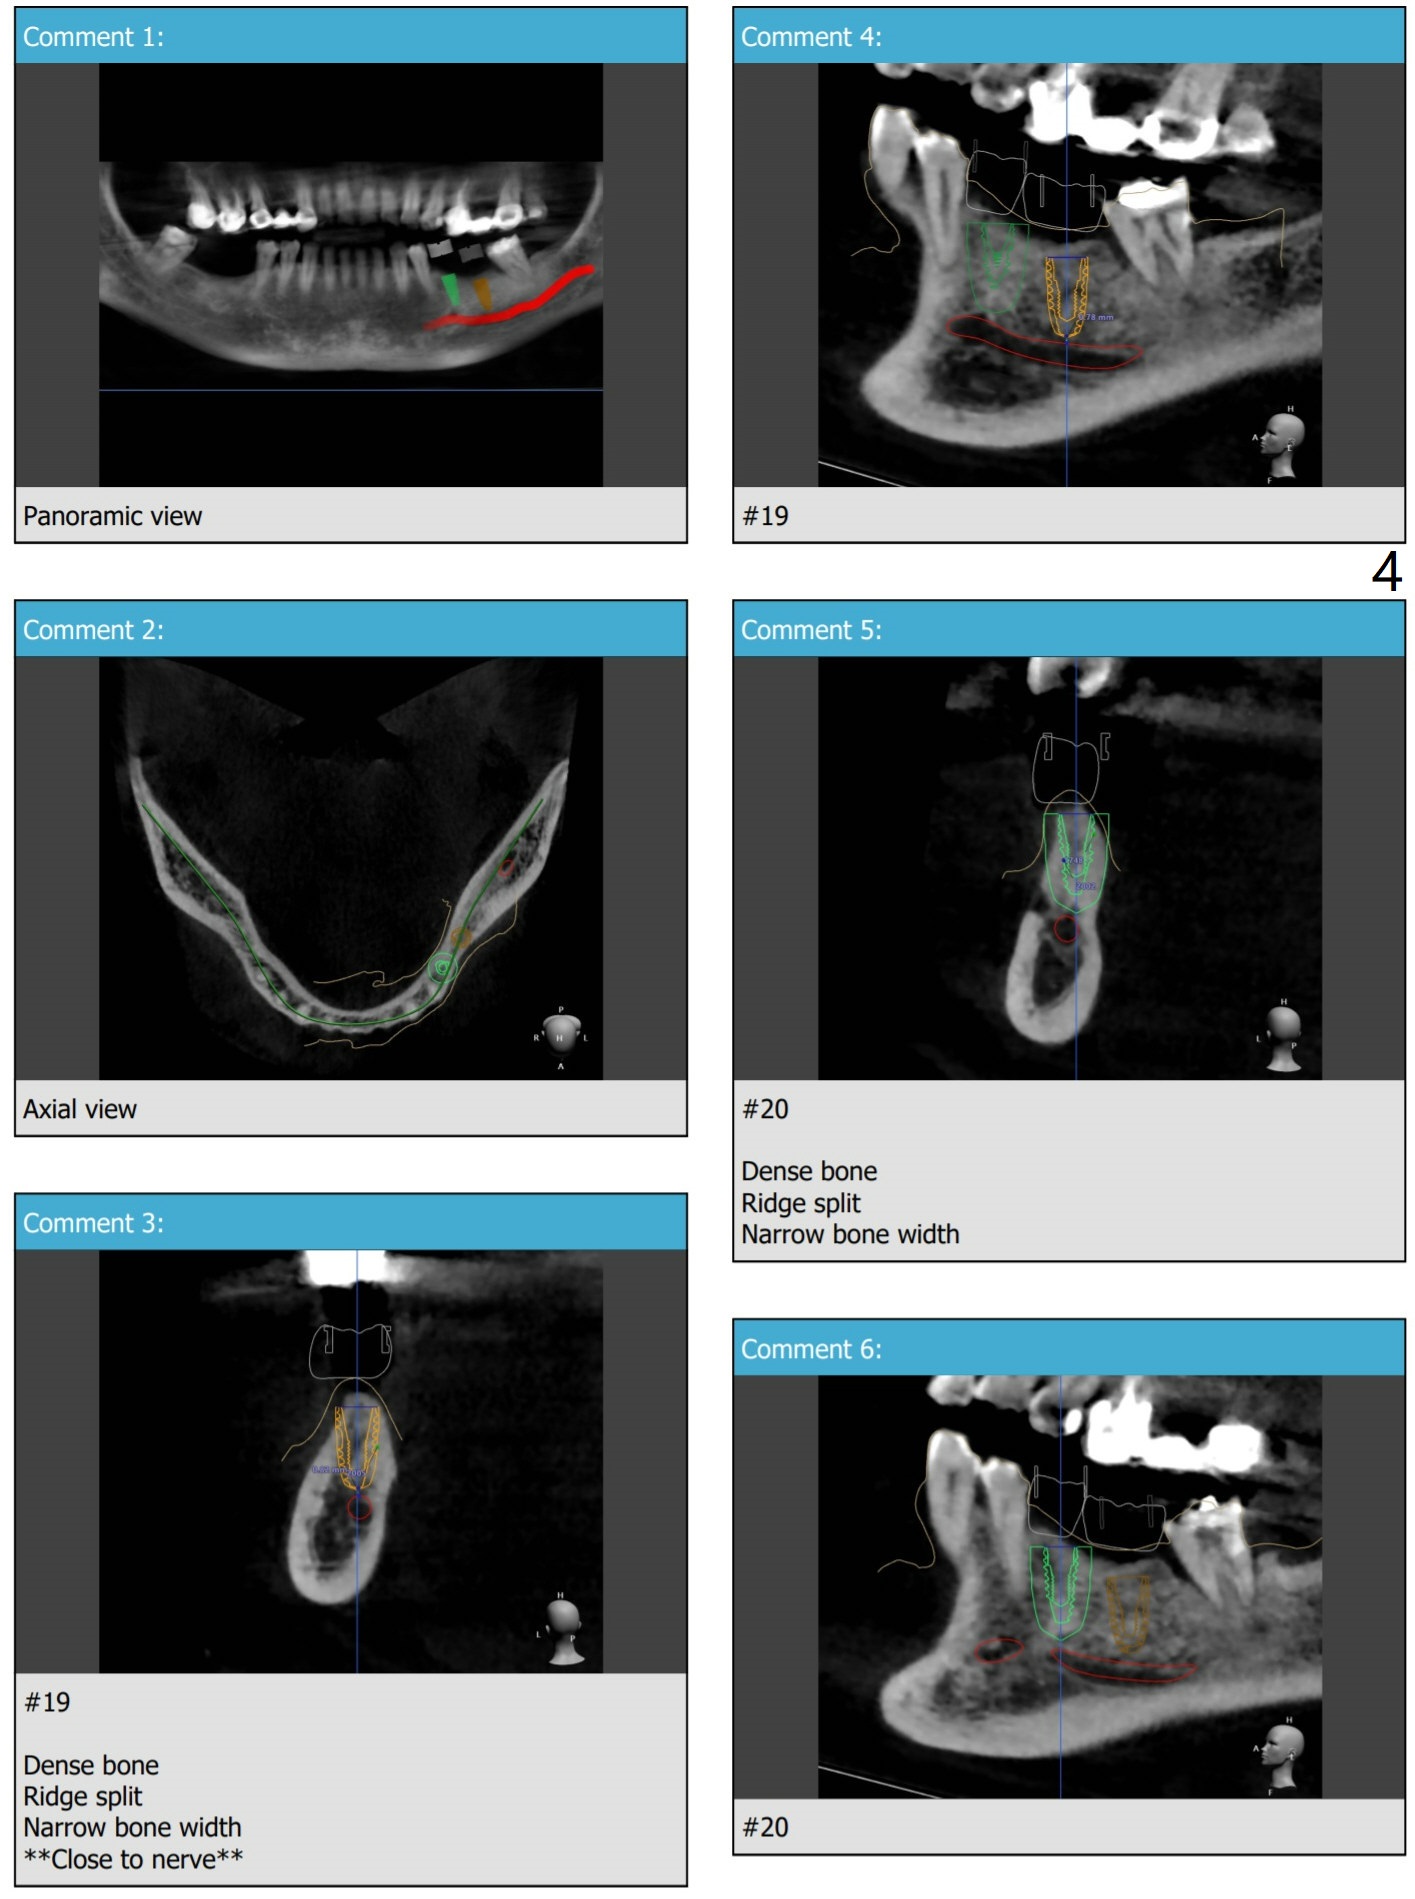

接近神经

For split, prepare, wheel bone saw, blade osteotomes, surgical handpiece (new skinny bur), IBS Surgical Kit (Magic Split)